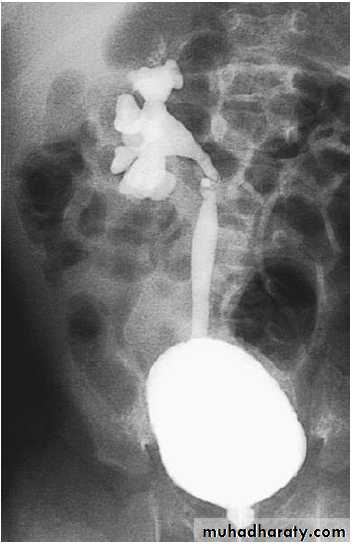

VSUG: showing

G 4 right VURTREATMENT